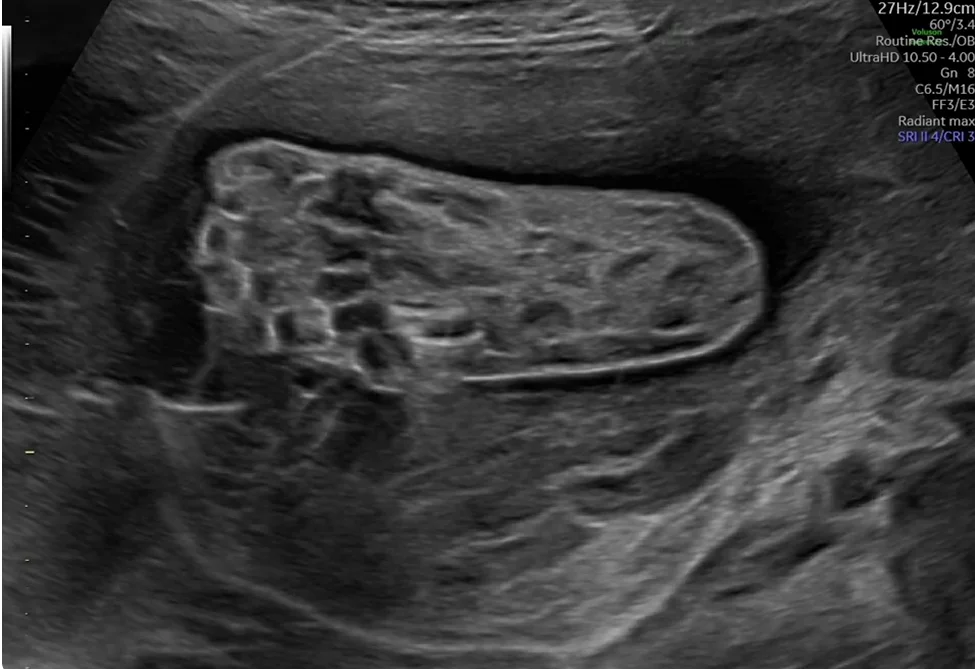

• Tật lưỡi to thai nhi (Macroglossia)